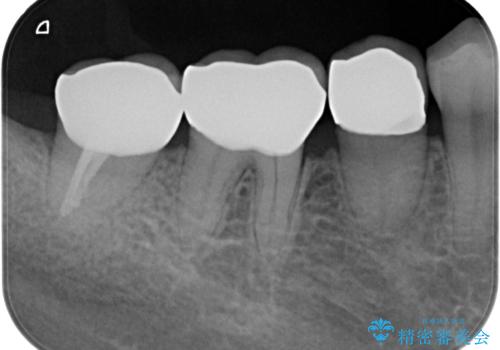

- 右下奥歯(7番)の高さがなく、かぶせ物(クラウン)にするためにあらかじめ歯周外科手術を行いました。(クラウンレングスニング)

特に根尖に症状がなかったため、右下7番の根管治療はやり直していません。

今回は右下7番が神経のない歯だったため、クラウンにして割れにくくしています。